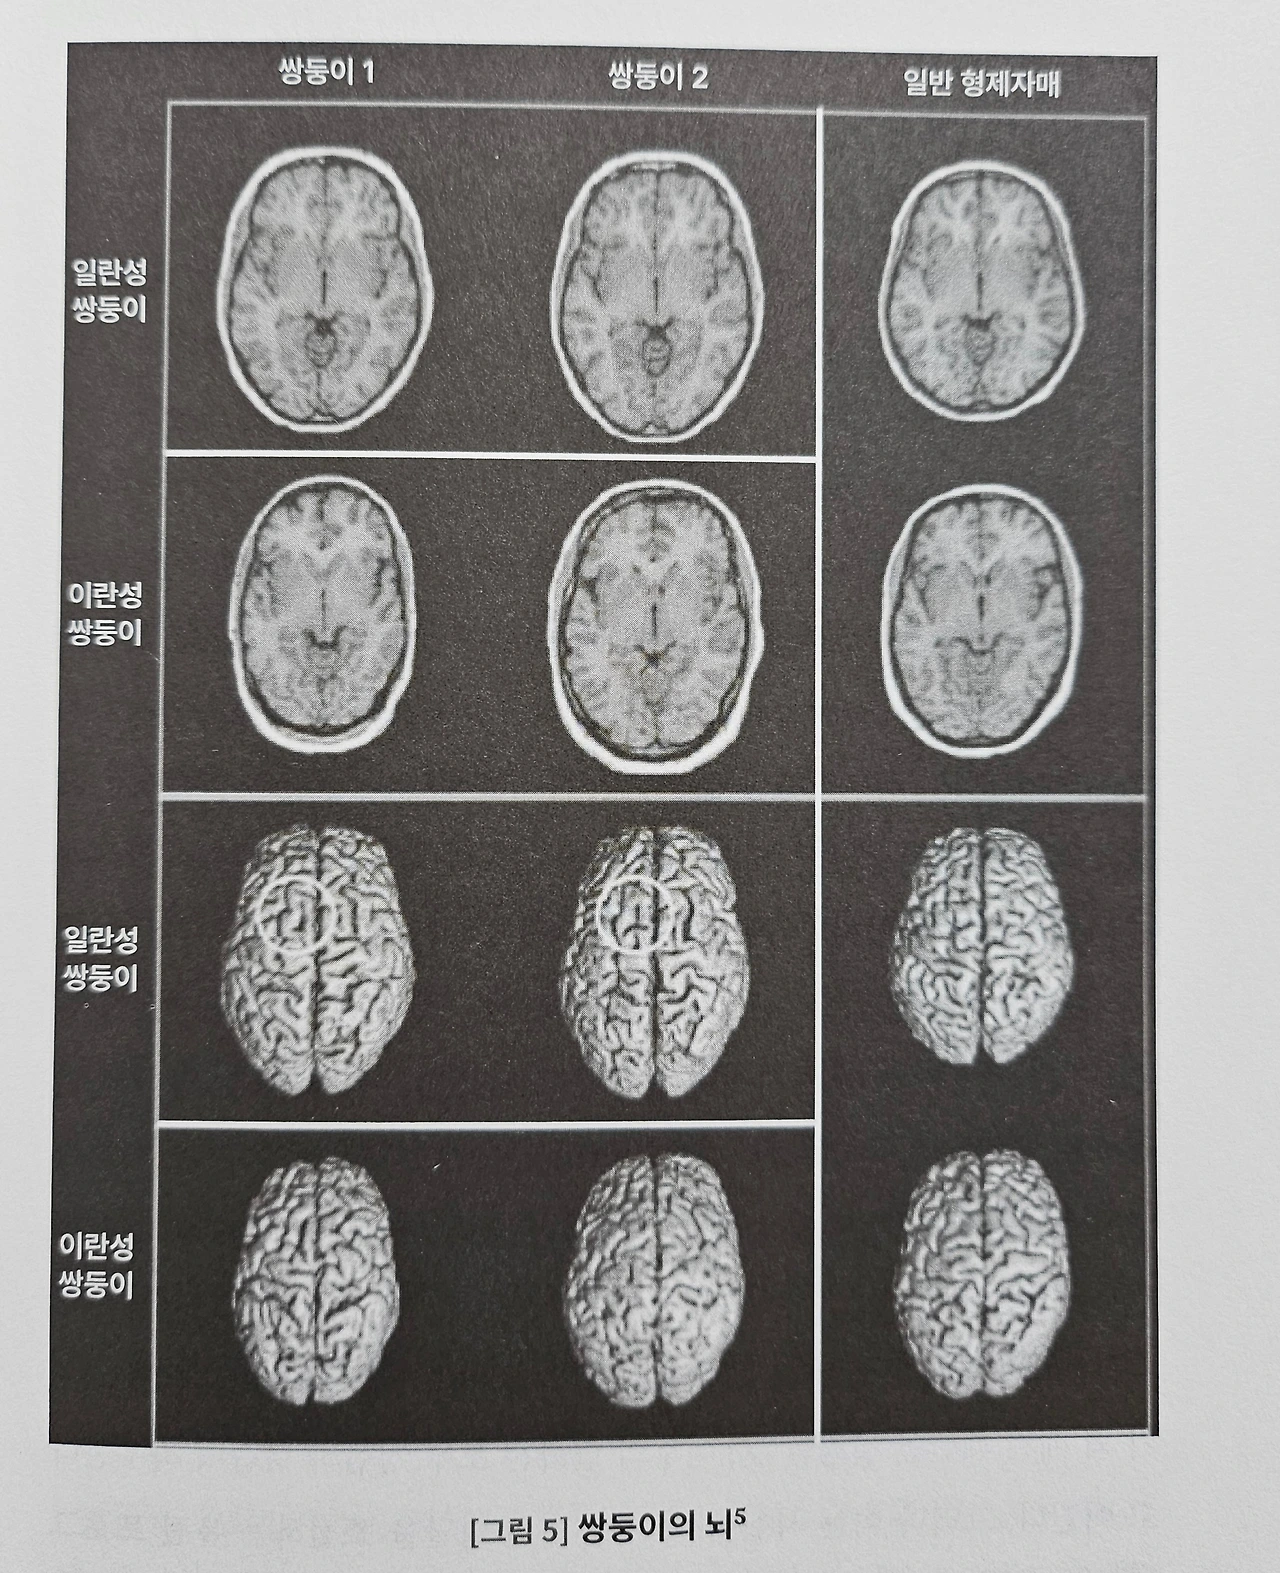

탄생 이전부터 지금의 모습에 이르기까지! 한권으로 읽는 무한한 내면 세계의 지형도 ! <우리는 무엇을 타고 나는가>는 우리의 정체성이 어떻게 만들어지며, 어느 지점에 서 있는가를 밝히는 작품으로 , 유전과 환경, 그리고 인간의 본성과 가능성에 대해 이야기를 다루는 뇌과학이다. 이 작품은 인간의 정체성과 행동을 형성하는 유전, 환경, 그리고 경험의 복합적인 상호작용을 탐구하는 신경유전학 기반의 교양 과학서이다. 인간의 성격, 지능, 성향은 유전과 환경의 단순한 합이 아니라, 무작위성과 상호작용의 결과라고 한다. "유전자가 모든 것을 결정한다"라는 것보다 개인의 다양성과 가능성을 말하는 작품이다. 뇌의 구조와 기능이 어떻게 유전적 프로그램에 따라 어떻게 형성이 되는지를 설명하고, 뇌 가소성과 후성 유전학을 통해 환경이 뇌에 미치는 영향도 함께 이야기하는 뇌과학 안내서이다. 이 작품은 유전자를 넘어 서로 다른 형질을 타고나 각자의 환경에서 자라 온 다양한 형태의 본성을 수용하고 맞아들이는 자세도 설명한다. 이 작품은 복잡한 우리 내면 세계의 지형을 전반부와 후반부로 나뉘는데, 전반부에서는 인간의 본성과 유전 연구의 기본 방법론, 뇌의 구조 및 기능 발달에 관한 신경과학적 기초와 환경 및 경험, 그리고 뇌 가소성을 다루고, 후반부에서는 이를 바탕으로 성격 특성과 지각, 지능, 성별과 신경 발달 질환이라는 구체적인 영역을 설명한다. 이 작품은 우리 뇌의 성장과 발달에 오랜 논쟁을 유발해 온 본성과 양육의 영역 가운데 무엇이 더 큰 힘을 발휘하는지도 논의한다. 그리고 현대 유전학의 성과가 인간 사회에 남기는 윤리적, 철학적 요인도 함께 설명한다.

성격, 감각, 지능, 성별, 성적, 지향, 정신 질환 등 다양한 인간 특성의 유전적인 요인과 환경적 요인도 분석하고, "우리는 백지로 태어나지 않는다" 라는 과학적 근거로 이야기한다. 유전자 쇼핑, 인종과 집단에 대한 유전 적용 등 현대 유전학이 던지를 사회적 비판도 함께 들어 있어서, 과학적 깊이 뿐만 아니라 철학적 깊이도 함께 다루고 있는 작품이어서, 자기 이해와 인간 이해에 관심 있는 분이라면 충분히 재미있게 읽을 수 있는 작품이다. 뇌는 유전적 청사지에 따라 형성이 된다고 한다. 하지만 무작위적인 신경 발달과 환경적 영향이 개개인의 차이를 만들어낸다고 말한다. 과학적 사실을 바탕으로 개인의 다양성과 가능성을 존중하는 태도의 중요성을 이야기하는 이 작품은 우리는 얼마나 타고난 존재인지, 유전자가 우리 삶의 방향을 결정하는지, 아니면 가능성을 여는 열쇠인지, 혹은 인간의 정체성은 어떻게 형성되는지에 대해 다루는 작품으로, 단순한 과학책이 아니라, 인간 존재에 대한 깊은 철학적 성찰을 담고 있는 작품이다.